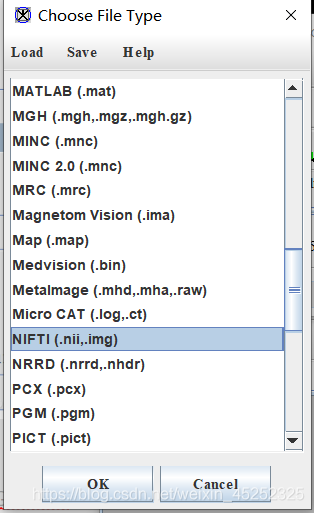

(7)保存:在主界面上点击file-save image as,然后选择要保存的格式,进行图片保存

一般选择nii格式